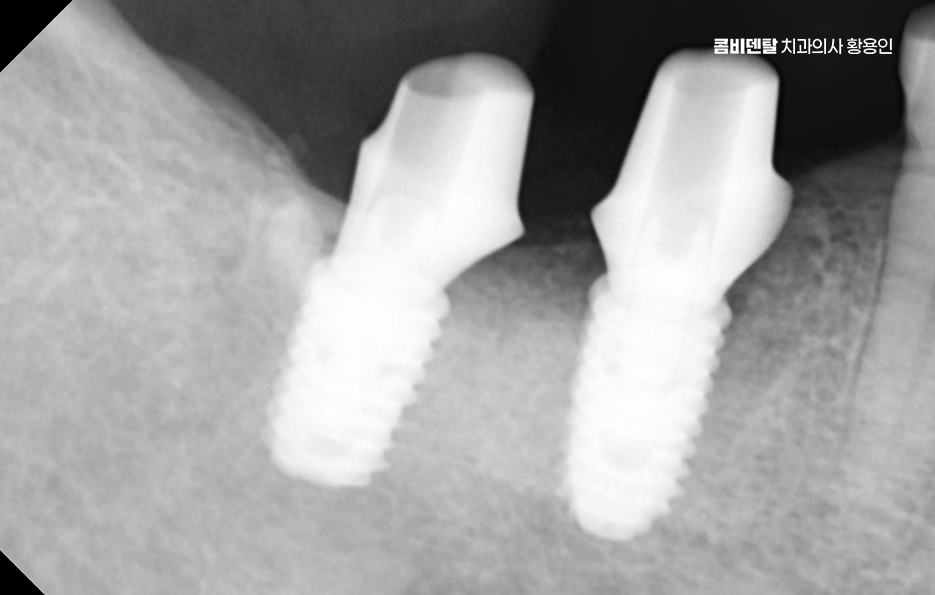

어금니 임플란트 과정에서 수술 당일에는 국소마취 후 잇몸을 절개하거나 최소 절개로 접근해 뼈에 임플란트를 식립하며 수술 후에는 일정 기간 골유착을 기다리는데 임플란트와 뼈가 단단히 결합하는 과정이라 할 수 있었어요

골유착이 완료되면 지대주를 연결하고 본을 떠서 최종 보철물을 제작하며 어금니 크라운은 강도와 교합 조화를 동시에 고려해 제작하는데 씹는 힘이 집중되는 부위이기 때문에 높이와 접촉점 조정이 중요하며 교합이 맞지 않으면 나사가 풀리거나 보철물에 문제가 생길 수 있어서 장착 후에도 교합 점검 및 정기적인 검진, 스케일링 등의 관리가 중요할 수 있어요

흔히 임플란트는 충치가 생기지 않는다고 생각하는 경우가 많은데 잇몸 염증은 충분히 생길 수 있으며 임플란트 주위염이 발생하면 뼈가 녹아 실패로 이어질 수 있어서 치간칫솔이나 치실을 사용해 꼼꼼히 관리하고, 정기 검진을 통해 뼈 상태를 확인해야 하고 특히 어금니는 음식물이 잘 끼는 위치라 더 신경 써야 한다는 점에서도 치료 계획 만이 아니라 유지 관리까지 포함한 장기적인 케어가 중요하다고 볼 수 있었어요